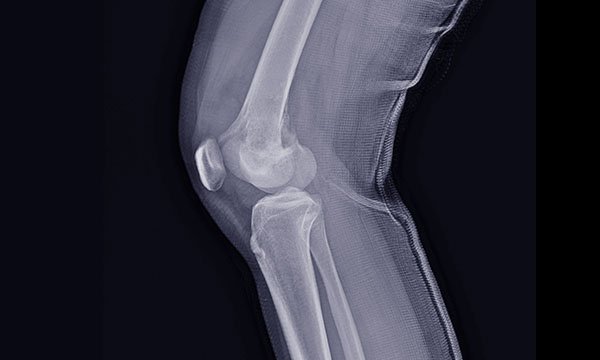

Nurses working in ED need to know how to assess, manage and refer patients with a bone tumour